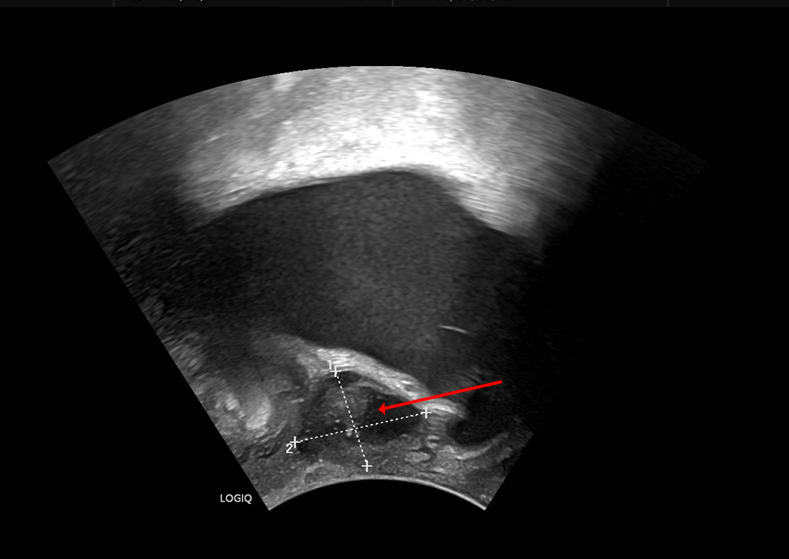

Aktuelles Thema: "Unklare Raumforderung zwischen Vagina und Urethra bei einer 62-jährigen Patientin"